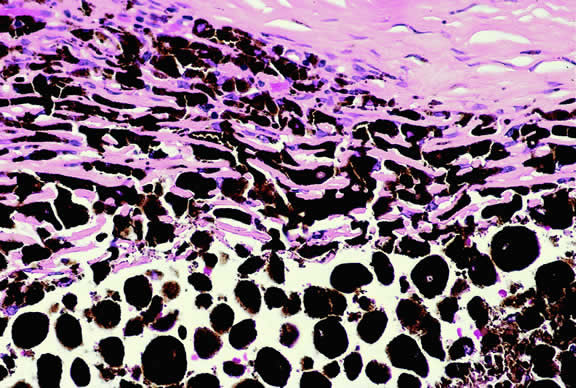

The substrate for the development of melanoma in white patients with ocular melanocytosis is a diffuse nevus that affects all, or part, of the uveal tract. Clinically, the nevus typically is evident as hyperchromic heterochromia iridum, patchy slate gray epibulbar pigmentation, and a darker aspect of the fundus compared with the fellow eye (Fig. 8). A sector of uvea is affected in some patients, however, and the nevus may spare the iris. The uvea in congenital melanocytosis is thickened by an increased number of heavily pigmented nevus cells similar to those found in melanocytomas (Fig. 9). RPE abnormalities such as drusen often develop on the surface of the thickened choroid.48 The sclera also contains patchy foci of pigmentation. The slate gray conjunctival pigment reflects the presence of dendritic melanocytes on the epibulbar tissues deep to the conjunctiva. Nevus of Ota does not predispose to conjunctiva melanoma. However, patients rarely may develop melanomas of the orbit49–51 and even leptomeninges.1,52,53 White patients who have congenital ocular or oculodermal melanocytosis should be followed periodically because of the increased risk of uveal melanoma.54

Fig. 9. Congenital ocular melanocytosis, choroid. Choroidal stroma is thickened by infiltrate of heavily pigmented benign melanocytes. Patient had iris heterochromia and skin pigmentation consistent with nevus of Ota. (Hematoxylin-eosin, × 100.)